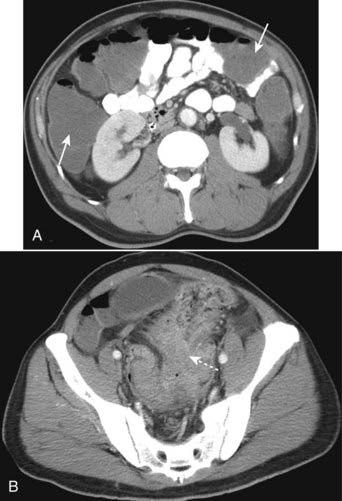

imageRecognizing renal cell carcinoma on CT:

image A dedicated CT scan for renal cell carcinoma usually consists of images obtained before and after intravenous contrast administration.

image Ranging from completely solid to completely cystic, renal cell carcinomas are usually solid lesions which may contain low-attenuation areas of necrosis. Even though renal cell carcinomas enhance with intravenous contrast, they still tend to remain lower in density than the surrounding normal kidney.

image Renal vein invasion occurs in up to one in three cases and may produce filling defects in the lumen of the renal veins (Fig. 18-38A).

image On ultrasound, smaller renal cell carcinomas are usually hyperechoic; as the lesion increases in size and undergoes necrosis it may be hypoechoic. Its wall, however, should be thicker and more irregular than a simple cyst (Fig. 18-38B).

Figure 18-38 Renal cell carcinomas CT and US.

A, There is a low-density mass involving the anterior portion of the left kidney (solid white arrow). The tumor is seen to extend directly into the left renal vein (solid black arrow), a propensity for renal cell carcinomas. B, Sagittal ultrasound on another patient with renal cell carcinoma shows an echogenic mass (M) occupying the mid portion of the kidney (dotted white arrows).